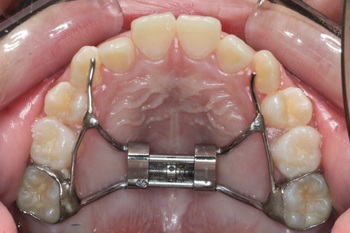

1. 急速拡大装置とは?

急速拡大装置は、上顎の骨に装着し、装置の中央にあるネジを少しずつ回すことで、上顎の骨を側方に広げる矯正装置です。

取り外し不可: 装置は歯にセメントで固定するため、お子様自身で取り外すことはできません。

短期間で効果: 顎の骨がやわらかい子どもの時期に行うことで、数週間から数ヶ月という比較的短期間で効果が得られます。

骨自体を広げる: 歯を外側に傾けるのではなく、骨自体を広げるため、後戻りしにくいのが特徴です。

ステップ2:装置の装着と拡大

ステップ3:保定期間